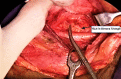

The magnification technique offered by surgical loupe is a new method that enhances visualization and helps head and neck surgeons with recurrent laryngeal nerve (RLN) and parathyroid glands identification. This study aimed to assess the safety and efficacy of using binocular surgical loupes in thyroidectomy procedures.

Material and methods: Eighty patients with thyroid nodules who underwent thyroidectomy procedure were divided randomly into two comparable groups, group A subjected to thyroidectomy by using binocular magnification loupe, group B underwent conventional thyroidectomy without using magnification. Patients' demographics, operation time, and postoperative morbidities were recorded. All cases had preoperative and postoperative vocal cords assessment by video laryngoscopy. Pathology, laboratory, and radiology investigations were also conducted.